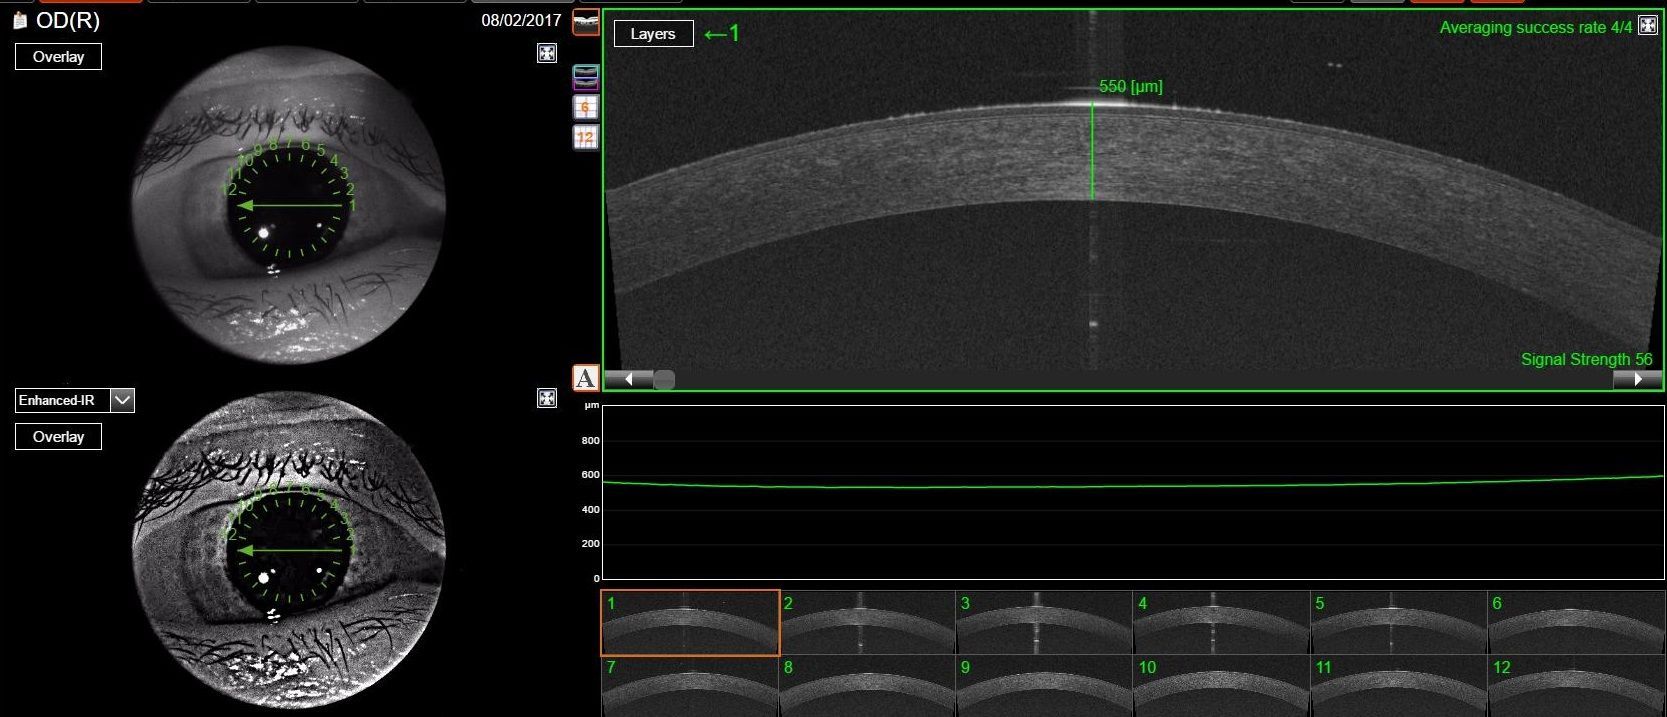

• Pachimetria, esame che serve a interpretare nel modo più corretto i valori della pressione oculare

• Analisi della cornea, per studiare le diverse patologie corneali

• Esame della camera anteriore, per valutare eventuali rischi di glaucoma acuto ed eventuali indicazioni all'iridotomia

La tomografia ottica computerizzata (OCT) è un esame che rappresenta un passo fondamentale nella diagnostica oculistica avanzata. Questo innovativo metodo diagnostico è completamente non invasivo e offre la possibilità, senza causare alcun dolore al paziente, di ottenere scansioni straordinariamente precise e ad alta risoluzione della cornea e della retina. Grazie alla tecnologia all'avanguardia della OCT, effettuata presso lo studio oculistico della dottoressa Tormene, è possibile non solo monitorare la salute degli occhi, ma anche identificare con tempestività un ampio ventaglio di patologie corneali, retiniche e del nervo ottico. Questa precoce individuazione consente ai medici di intervenire in modo efficace, applicando la terapia più adatta alle specifiche esigenze del paziente, garantendo così una migliore prognosi e una maggiore qualità della vita visiva.

L’OCT “Triton”, si basa sull’acquisizione di immagini digitali con la recente tecnica dello swept-source, che migliora di molto la velocità e la sensibilità di registrazione.

La tecnica è particolarmente precisa, veloce (fino a 100.000 Ascan/sec) e le immagini che fornisce sono estremamente dettagliate, con una profondità di campo tale da consentire di ottenere una sola immagine dal vitreo alla coroide.

Il particolare sistema di eye traacking usato dallo strumento in possesso dello studio è in grado di seguire eventuali movimenti dell’occhio del paziente mantenendo la precisione delle immagini.

In molti casi questa caratteristica consente alla dottoressa Tormene di eseguire l’esame senza dover effettuare la dilatazione della pupilla del paziente.